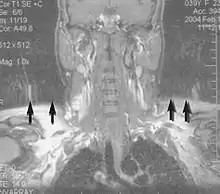

Motion artifact (T1 coronal study of cervical vertebrae)[139]

An MRI artifact is a visual artifact, that is, an anomaly during visual representation. Many different artifacts can occur during magnetic resonance imaging (MRI), some affecting the diagnostic quality, while others may be confused with pathology. Artifacts can be classified as patient-related, signal processing-dependent and hardware (machine)-related.[139]